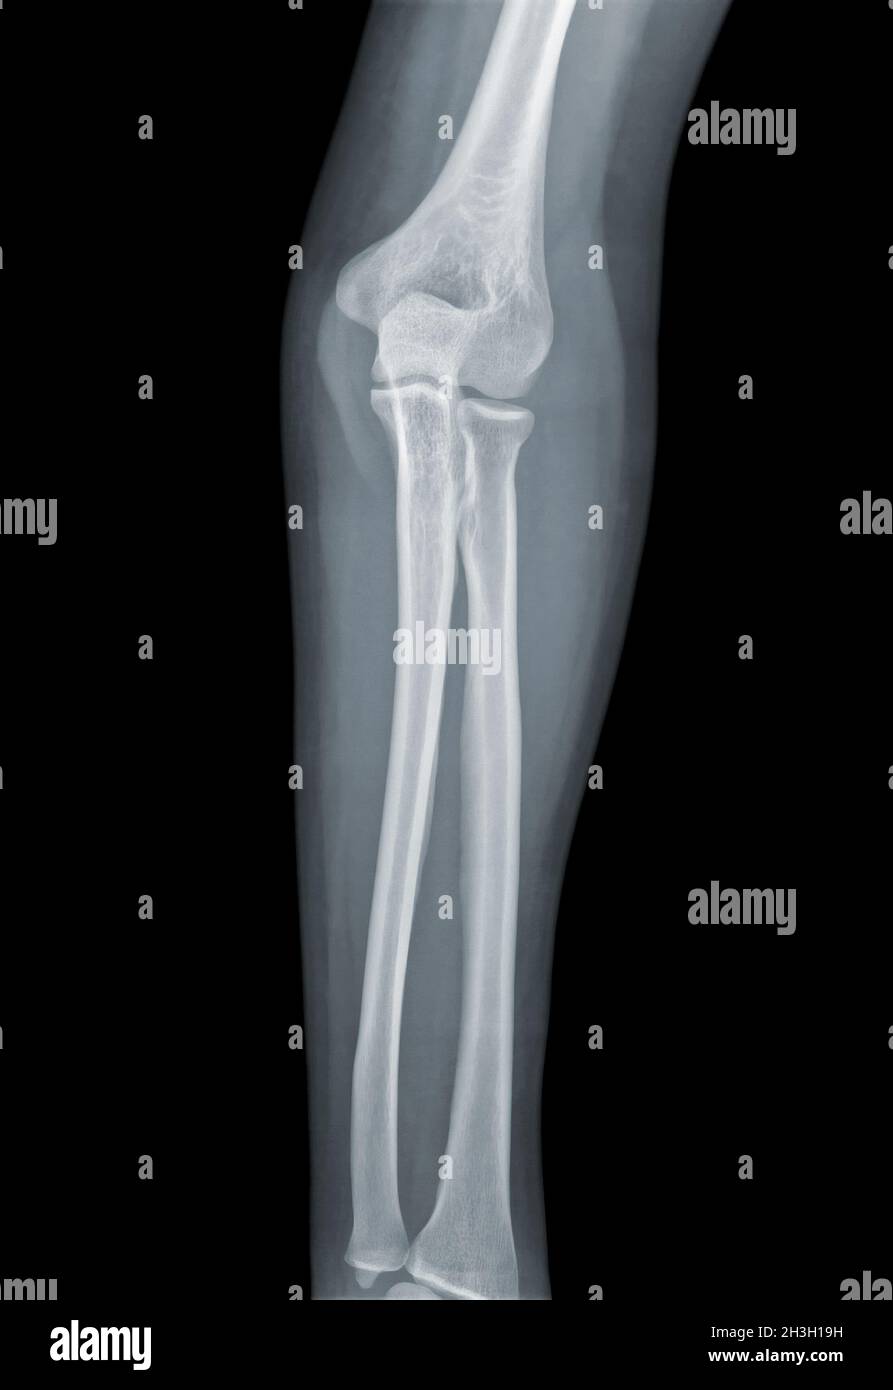

Left Elbow X-Ray Film . In adults, elbow dislocation is the second most common. Web the elbow series is a set of radiographs taken to investigate elbow joint pathology, often in the context of trauma.

Fractures lines can be difficult to visualize after acute elbow injury, particularly in children. The osseous anatomy of the elbow is complex, and fractures can occasionally be radiographically occult or. Web this view is clinically indicated for trauma to, chronic discomfort or infection of the elbow joint.

Web this view is clinically indicated for trauma to, chronic discomfort or infection of the elbow joint. It aids in visualizing fractures and/or. Web elbow fractures and dislocations are commonly seen in the acute care setting. Fractures lines can be difficult to visualize after acute elbow injury, particularly in children.

Left Elbow X-Ray Film - In adults, elbow dislocation is the second most common. The osseous anatomy of the elbow is complex, and fractures can occasionally be radiographically occult or. Web the elbow series is a set of radiographs taken to investigate elbow joint pathology, often in the context of trauma. Your elbow bones include the upper bone of your elbow joint (humerus) and the..